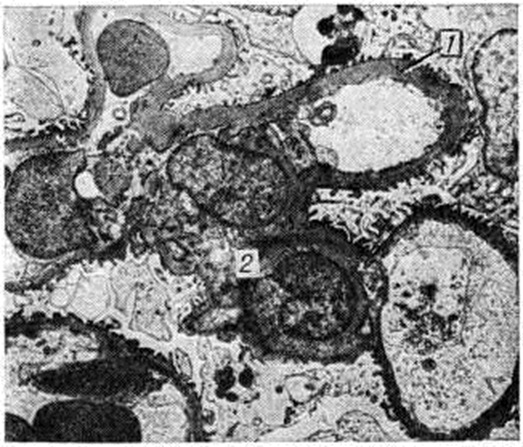

Гломерулосклероз диабетическийГломерулосклероз диабетический (латинское glomerulus клубочек + склероз; греческий diabetes, от diabainein проходить; синонимы: интеркапиллярный гломерулосклероз, синдром Киммелстила — Уилсона) — специфическая и наиболее частая форма поражения почек при сахарном диабете; впервые описана в 1936 году. Гломерулосклероз диабетический является одним из наиболее тяжёлых осложнений сахарного диабета (смотри полный свод знаний Диабет сахарный). Частота Гломерулосклероз диабетический по материалам аутопсии колеблется от 19,5% [Хендерсон (L. Henderson)] до 50,9% [Уайт (White)] у больных, страдающих сахарным диабетом свыше 20 лет. В клинике Гломерулосклероз диабетический, по данным Р. А. Хейфец и Л. И. Каминской, выявляется в 6%, по данным Э. Глоссит Москович — в 17,8% и даже в 48% случаев (В. В. Сура) от числа больных, страдающих сахарным диабетом. У женщин, страдающих сахарным диабетом, Гломерулосклероз диабетический встречается в 30%, у мужчин — в 19,5% случаев. Патологическая анатомияГистологические изменения почек при Гломерулосклероз диабетический весьма полиморфны; выделены три основных формы поражения — узелковая, диффузная и экссудативная. Некоторые авторы вместо экссудативной выделяют смешанную форму. Узелковая форма характеризуется наличием в клубочках эозинофильных образований (узелков) округлой или овальной формы (рисунок 1), содержащих вакуоли. Они могут занимать часть или весь клубочек, по периферии которого в последнем случае располагаются сохранившиеся сдавленные капиллярные петли. Одновременно наблюдается расширение и аневризмы капилляров клубочков, утолщение их базальных мембран. При гистохимическом исследовании узелков они вначале окрашиваются как фибрин, а в дальнейшем как коллаген. Узелки содержат большое количество высокомолекулярных мукополисахаридов, небольшое количество кислых мукополисахаридов, жировых субстанций, в основном ненасыщенных жирных кислот и холестеринэстеров. При электронно-микроскопическом исследовании видно, что формирование узелков происходит в мезангии в виде скопления в нем глыбок и трабекул, сходных с веществом базальной мембраны. Диффузная форма выражается в однородном расширении и уплотнении мезангия с вовлечением в процесс базальных мембран капилляров, которые резко утолщены. Образующиеся в мезангии мембраноподобные структуры не сливаются в сплошные массы, и образования узелков не происходит. Базальные мембраны капиллярных петель клубочков утолщены, структура их исчезает (рисунок 2). Смешанная форма характеризуется сочетанием типичных узелков с диффузным уплотнением мезангия и утолщением базальных мембран капилляров клубочков (рисунок 3). По данным электронно-микроскопических исследований утолщение базальных мембран капилляров клубочков возникает рано, нередко до появления каких-либо клинических проявлений поражения почек, и имеет место, видимо, при всех формах Гломерулосклероз диабетический Утолщение мембран наблюдается не только у больных, но и у молодых людей из диабетически отягощённых семей. Экссудативная форма встречается реже, чем предыдущие, и характеризуется прежде всего так называемый «фибриноидными шапочками», которые представляют собой отложения PAS-положительного материала между эндотелием и базальной мембраной капилляров (рисунок 4). При иммуногистохимическом исследовании в этих образованиях обнаруживается значительное количество комплементсвязывающих иммуноглобулинов, что даёт основание считать их комплексом антиген—антитело, а не сывороточным экссудатом. «Фибриноидные шапочки» не являются специфическими для Гломерулосклероз диабетический, но вместе с тем они обнаруживаются при тяжёлых и быстро прогрессирующих его формах. С ними часто сочетаются так называемый «капсульные капли», располагающиеся на внутренней стороне боуменовой капсулы. |